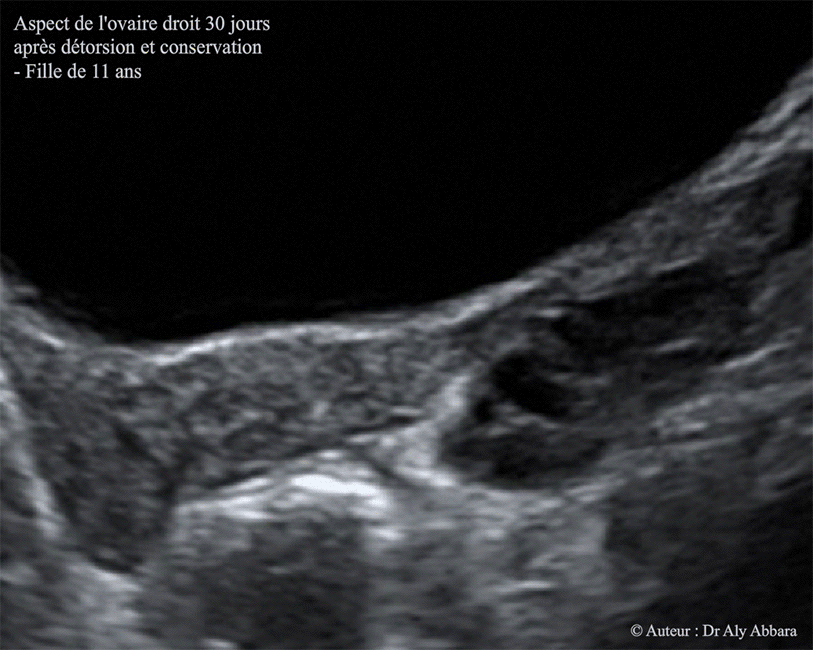

J30 :

Images échographiques montrant le même ovaire droit, 30 jours après la détorsion chirurgicale et la conservation des annexes droites : on remarque une diminution du volume de l'ovaire droit (20,7 x 19,4 x 14,4 mm, soit environ 2,9 cm3 contre 73 cm3 en pré-opératoire et 18 cm3 à j5).

L'écho-Doppler a pas permis de confirmer de la présence des signaux Doppler vasculaires).